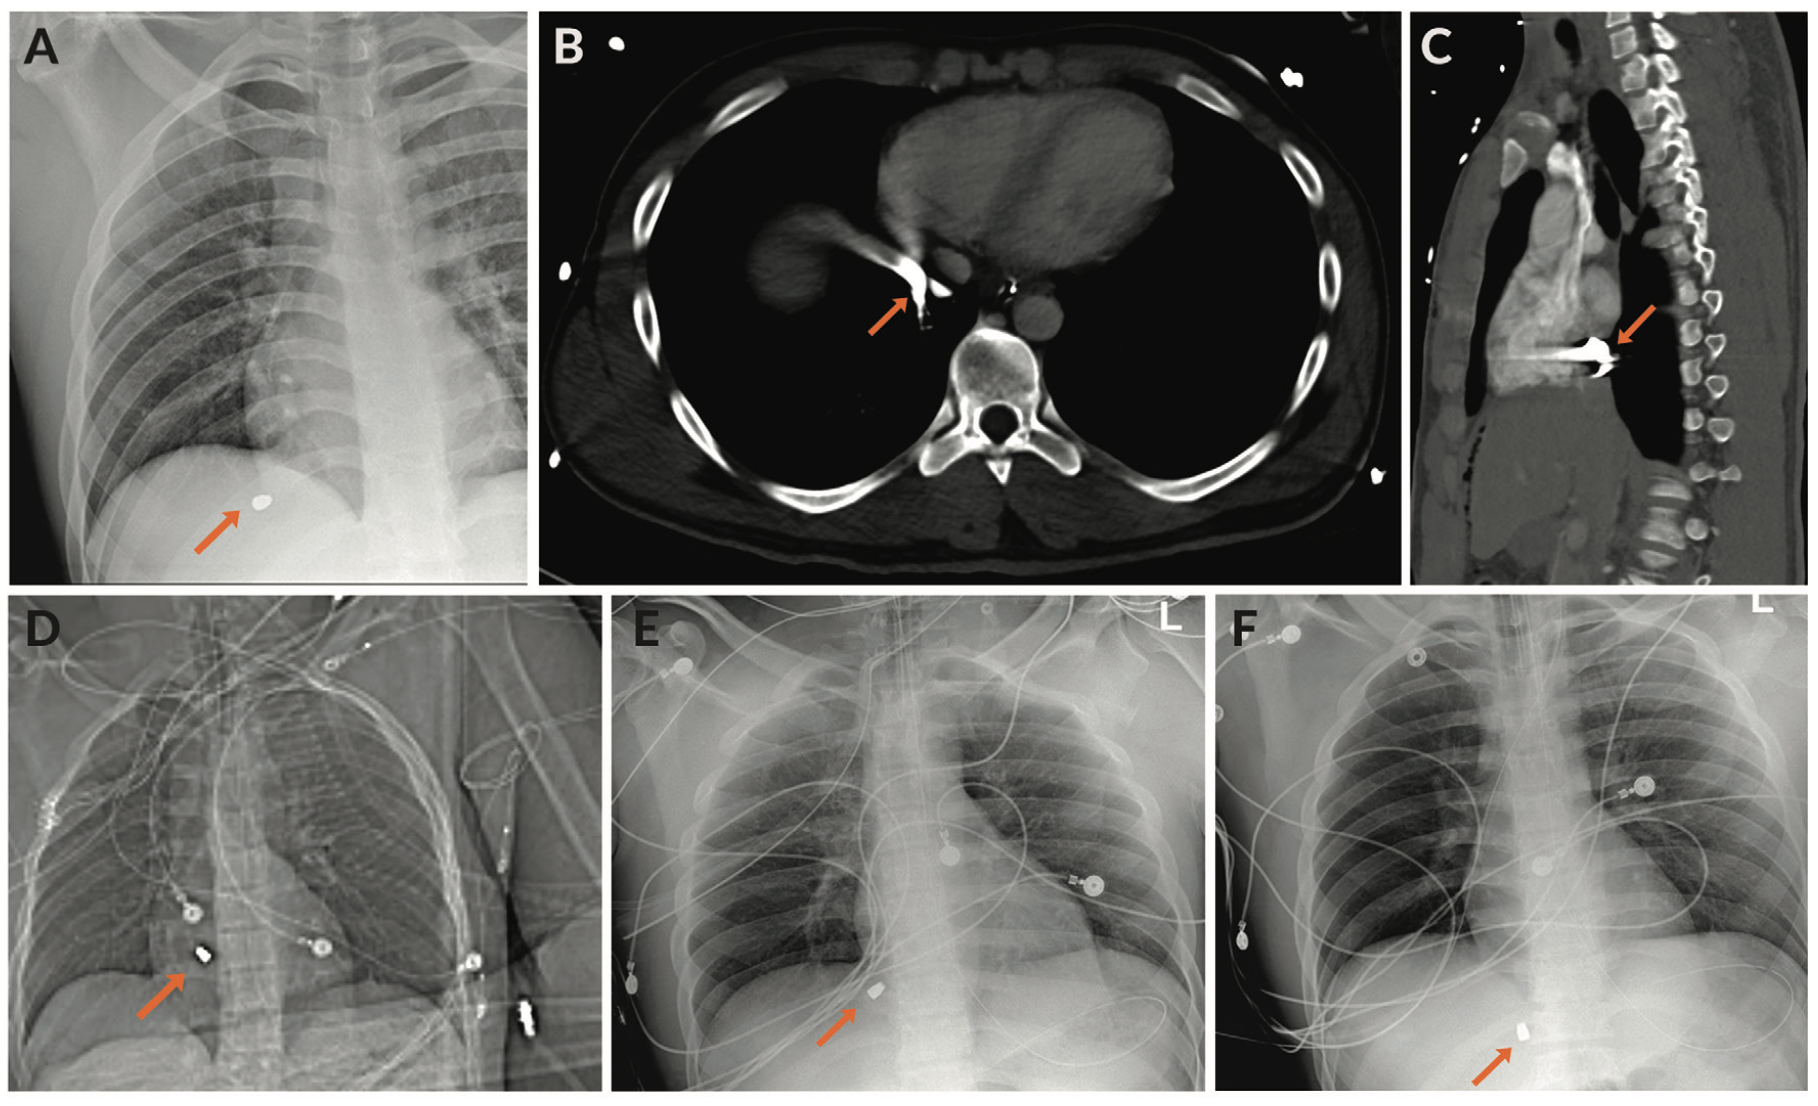

An extended focused assessment with sonography for trauma was positive for intra-abdominal fluid, likely blood products. Radiographs of the chest, abdomen, and pelvis were performed, and a bullet was noted in the high right upper quadrant of the abdomen under the right hemidiaphragm (Figure 2A). No exit wound was seen on physical exam.

The patient was brought to the computed tomography (CT) scan room for a CT of the chest, abdomen, and pelvis following trauma and urogram protocols. The scan was notable for a metallic bullet at the inferior cavoatrial junction (ICAJ). Subsequent chest radiographs demonstrated slight variation of the bullet, suggesting mobility and an intravascular location. The bullet projected over the upper IVC in multiple locations, also indicating mobility (Figure 2B-F).

Initial fluoroscopic images confirmed the bullet to be at the level of the ICAJ. It did not appear to be attached to the vascular or cardiac walls, as it moved freely from the right atrium to the ICAJ with cardiac and respiratory variation.

Subsequently, an 18-30 mm EN Snare Endovascular Snare System (Merit Medical) was assembled and advanced through the Protrieve sheath. Under fluoroscopy, the bullet was seen tumbling in the IVC at the ICAJ as the snare was utilized to capture it (Figure 3A, Video 1). The bullet was retracted through the mesh funnel and into the plastic sheath tip of the Protrieve sheath (Figure 3B, Video 2). The sheath was then retracted over the wire while tension was held on the bullet with the snare (Video 3). Fluoroscopy confirmed that the bullet did not move from the sheath tip and the bullet was then removed along with the sheath (Figure 3C-D). The sheath dilator was replaced into the venotomy site.